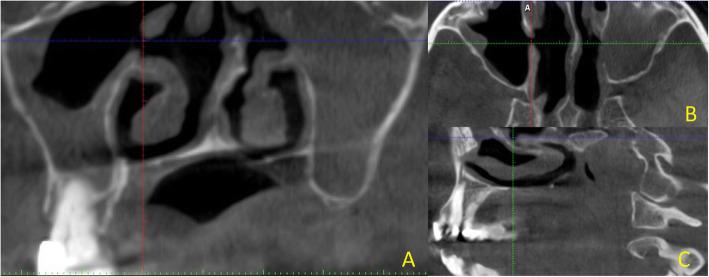

Accessory maxillary ostium (AMO) has a major role to play in the aetiology of maxillary sinusitis. Mucosal thickening is one of the key radiographic features of chronic maxillary sinusitis. The aim of this study was to identify the location of the AMOs and investigate the association between Mucosal Thickening [MT] and AMO using Cone Beam Computed Tomography [CBCT].

CBCT scans of 400 maxillary sinuses from the records of 200 patients who seeked various dental treatments at the Thumbay Dental Hospital, Gulf Medical University, Ajman, United Arab Emirates were evaluated. The incidence, anatomical position and maximal length of accessory maxillary ostia (AMO) in the maxillary antrum were reviewed using CBCT by two examiners. The association between MTs and AMOs were also analysed.

Among the 200 CBCT scans, 131 belonged to male patients and 69 scans belonged to female subjects within the age group of 18-65 years (mean age 41.32 years). AMOs were found in 142 maxillary antra (35.5 %). The inter-observer reliability for using CBCT to detect AMO was (k = 0.83). There was no significant difference in the frequency of AMOs when the age (P = 0.19) and gender (P = 0.54) distribution were considered. Sinuses with AMOs, showed significantly greater frequency of MTs (p = 0.001). AMOs with maximal length of less than 1mm were most commonly observed (51.40 %). AMOs with larger greater maximal length were associated with higher degrees of MT. The location of the AMOs, were not affected by the degree of MT.

The study demonstrates a clear association between degree of MT and occurrence of AMO in the maxillary sinus. However, the location of the AMO is independent of the degree of the MT. There is a greater probability of finding an AMO in the maxillary sinus if the MT in the sinus is more than 3 mm.